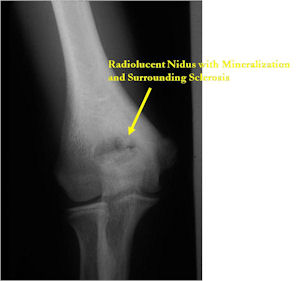

Plain X-Rays:

- Lucent nidus surrounded by a zone of marked sclerosis

- The nidus may demonstrate mineralization/ossification usually from the center outward that appears as a central zone of density within the nidus

- A nidus that is heavily ossified may blend in with the surrounding sclerosis and be difficult to detect on a plain x-ray.

- Periosteal bone is solid, rarely lamellated

- Cortical and subperiosteal osteoid osteomas are usually associated with much more reactive sclerosis than medullary tumors

- The periosteal reaction is continuous and often appears as cortical thickening (benign appearing reaction)

- Intracapsular osteoid osteomas are difficult to identify because there is no periosteum in the intracapsular region and hence a periosteal reaction does not occur.